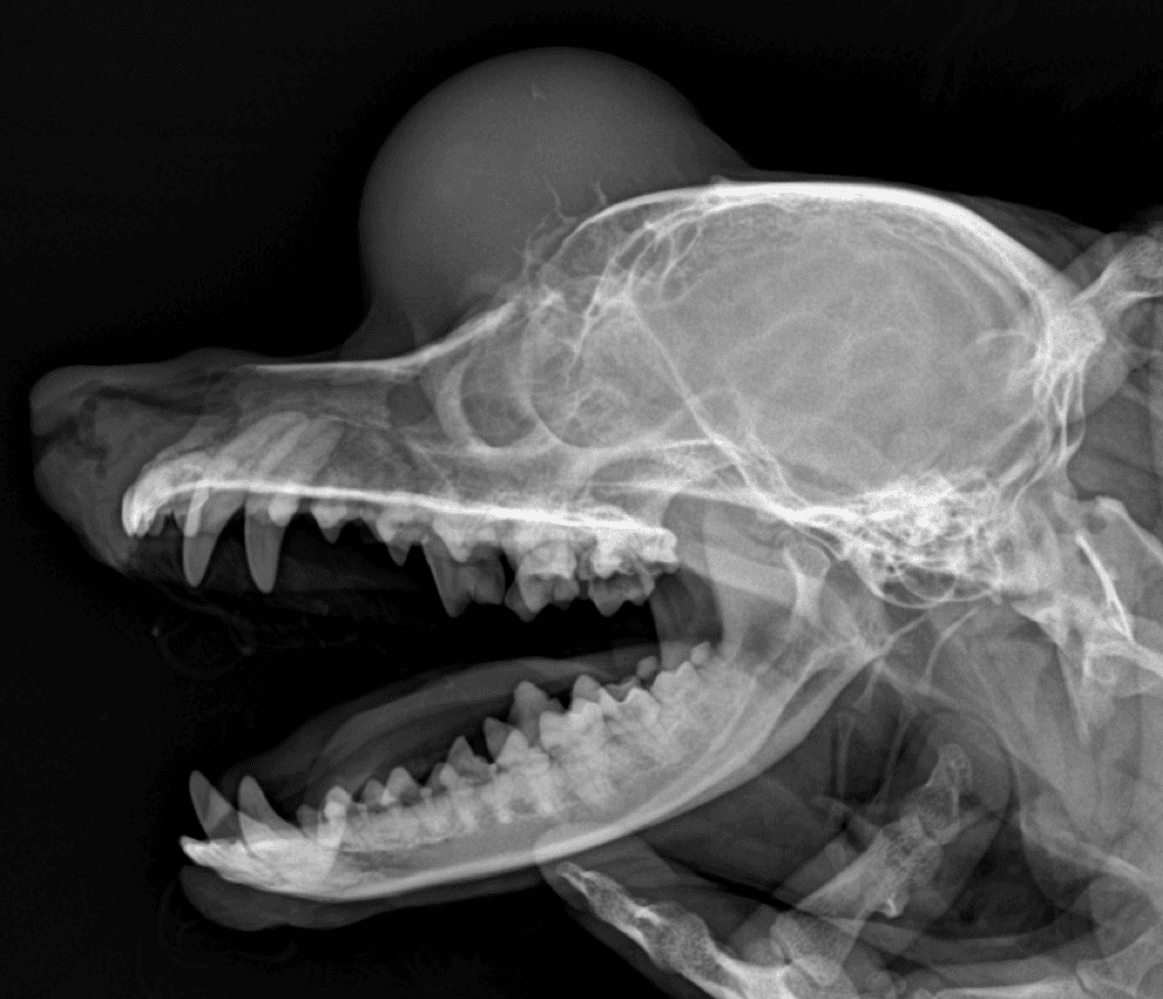

정형외과 전공의 수의사가 직접 수술합니다.

13수술 중 골절 상태 혹은 이식물 적용 후 상태 등 육안으로 명확히 확인하기 힘든 상태를 X-ray 확인하여 정확한 수술 결과를 만들어 내는 것이 가능

15치과 진단 및 치료시,육안으로 보이지 않는 치아상태 검진이 가능